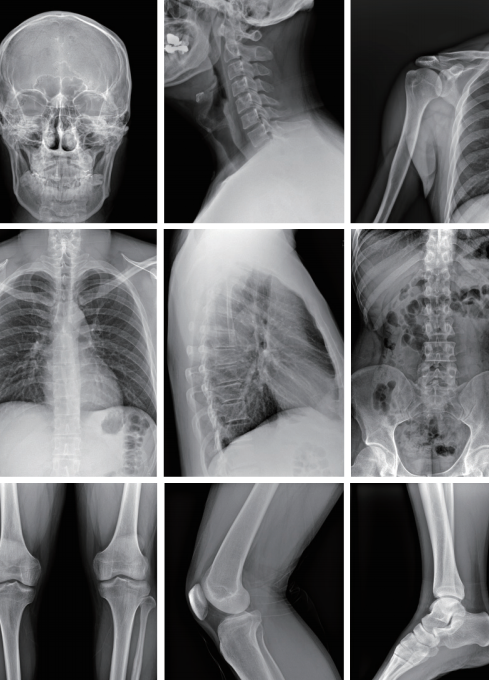

广与微

更大尺寸的成像范围, 形成更多的影像像素矩阵,易于涵盖拍摄部位的周围组织;

更大的图像矩阵 由数以千万计的微小像素单元构成, 提供给临床应用更清晰的影像。

高清影像

影像清晰,细节突出,无伪影

头颈正位片

灰阶对比突出,细节丰富

胸腰椎正位片

结构清晰,透视准确

图像分辨率高

空间分辨率可达5线对/毫米,密度分辨率优于传统胶片,能清晰显示骨结构、关节软骨及软组织细节